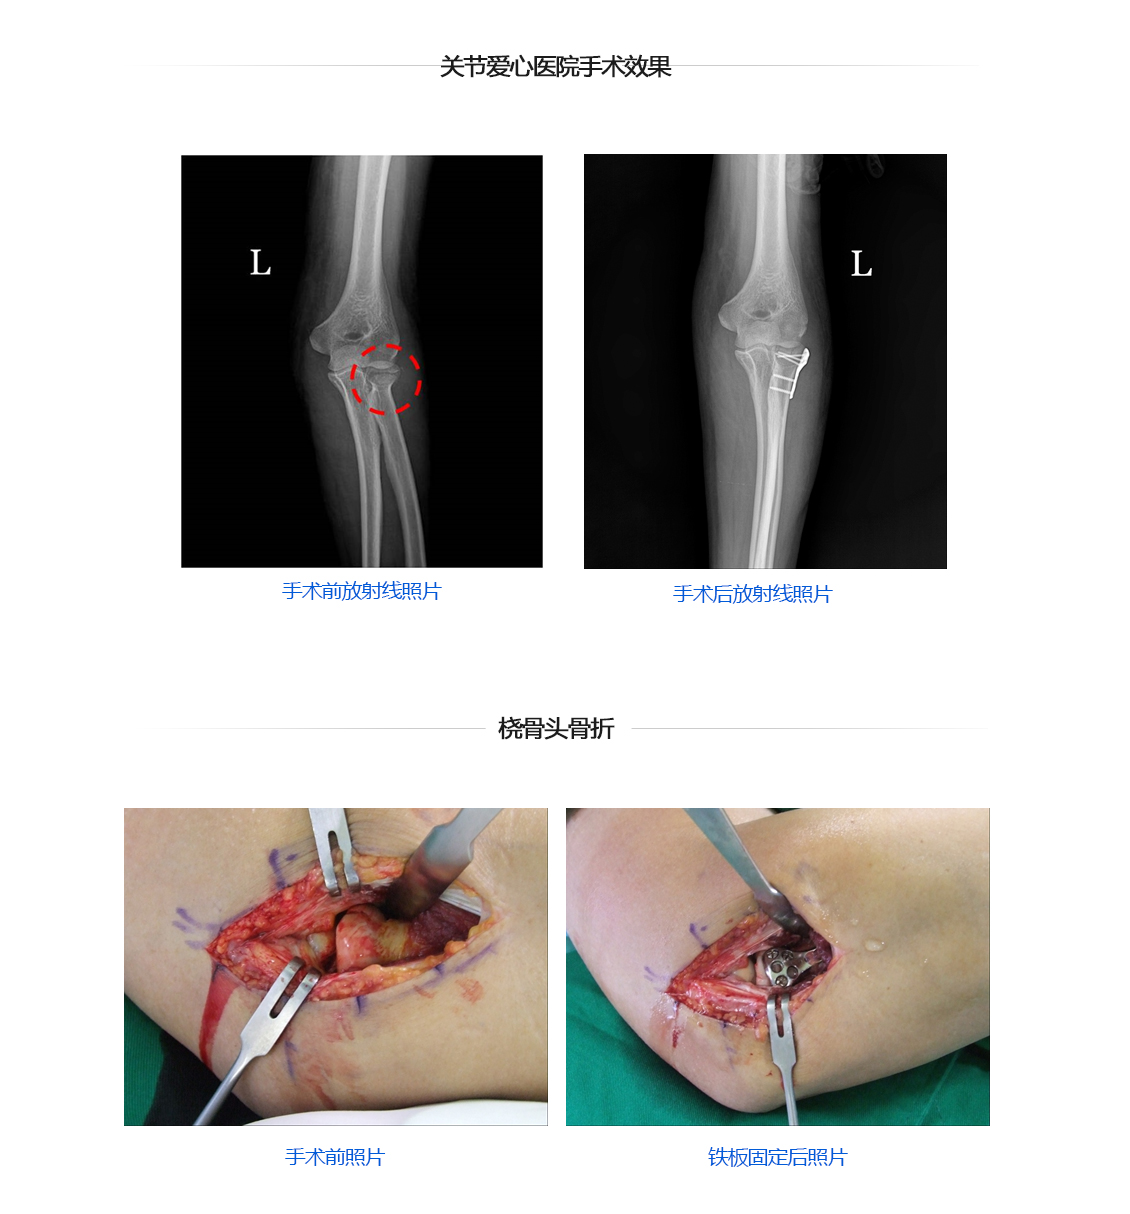

胳膊肘关节骨折